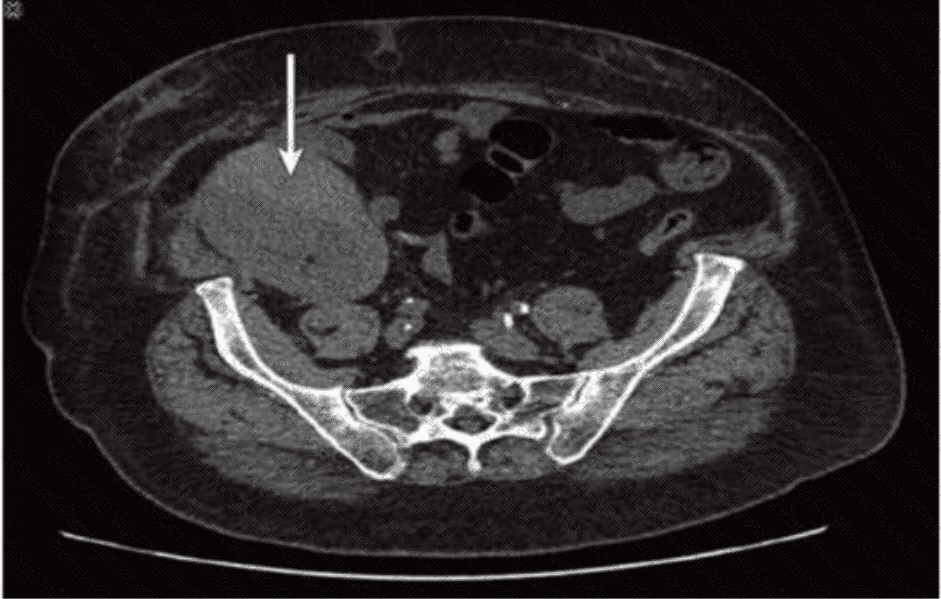

Which condition of the transplant kidney is indicated by the arrows on these images?